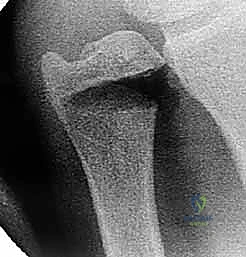

في الحالة الطبيعية، ينتهي كلا العظمين عند نفس المستوى تقريباً في مفصل الرسغ، وهو ما يُسمى بالتباين الزندي المحايد (Neutral Ulnar Variance). في هذه الحالة، يتحمل عظم الكعبرة حوالي 80% من القوة الضاغطة على الرسغ، بينما يتحمل الزند 20% فقط.

ولكن، عندما يكون عظم الزند أطول من عظم الكعبرة، تُعرف هذه الحالة بـ التباين الزندي الإيجابي (Positive Ulnar Variance).

ماذا يحدث عندما يكون الزند أطول من اللازم؟

حتى زيادة مقدارها 2.5 مليمتر في طول عظم الزند يمكن أن تزيد من القوة الضاغطة التي يتحملها من 20% إلى أكثر من 42%. هذا التحول الهائل في توزيع الأحمال يؤدي إلى سحق وسادة الغضروف الموجودة بين الزند وعظام الرسغ (TFCC)، مما يؤدي مع مرور الوقت إلى تمزقها وتآكل العظام المجاورة (مثل العظم الهلالي والعظم المثلثي).